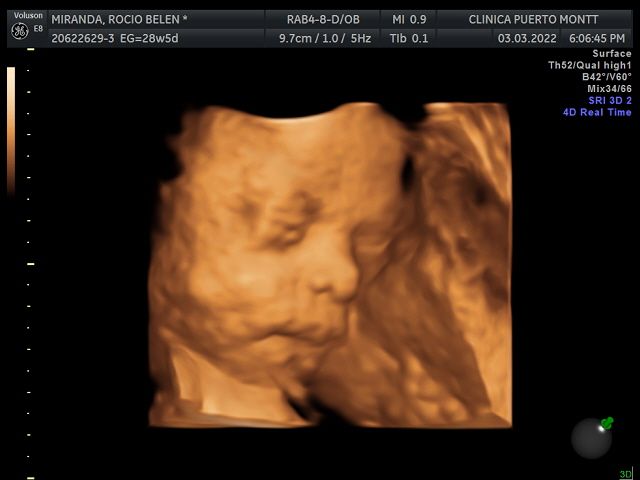

Ecografia Obstetrica y ginecologia

Ecografia Doppler obstetrica

Ecografia volumétrica (3 D y 4D)

Ecografía 4D 90000 $